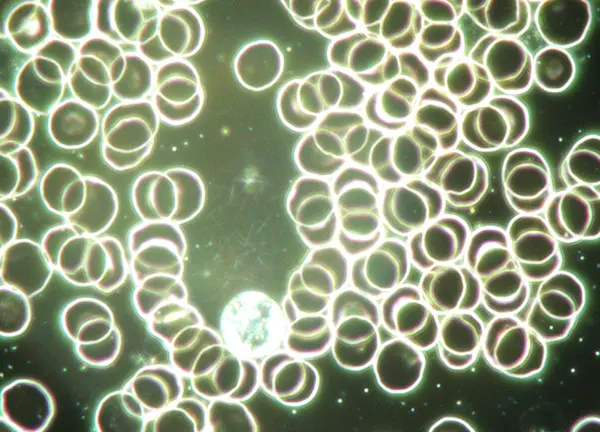

Bij een Levend Bloed Analyse (LBA) bekijken we samen, met behulp van een microscoop, een druppel levend bloed. Zo wordt zichtbaar wat er op cel- en bloedniveau speelt. Deze werkwijze geeft gericht inzicht in jouw gezondheid, maakt het mogelijk om resultaten helder in kaart te brengen, je proces te volgen en waar nodig bij te sturen.

Een Levend Bloed Analyse maakt zichtbaar wat zich op cel- en systeemniveau afspeelt, nog vóór het zich uit in klachten. Het biedt waardevolle inzichten in hoe jij je voelt, functioneert en wat je lichaam nodig heeft om in balans te komen – of te blijven.

Daar maakte ik voor het eerst kennis met Levend Bloed Analyse en het werken met Rife-frequenties. Het bloed laat helder zien wat er lichamelijk speelt, terwijl frequenties het zelfherstellend vermogen ondersteunen. Ik wist meteen: dit is wat ik te doen heb. Alles viel samen.